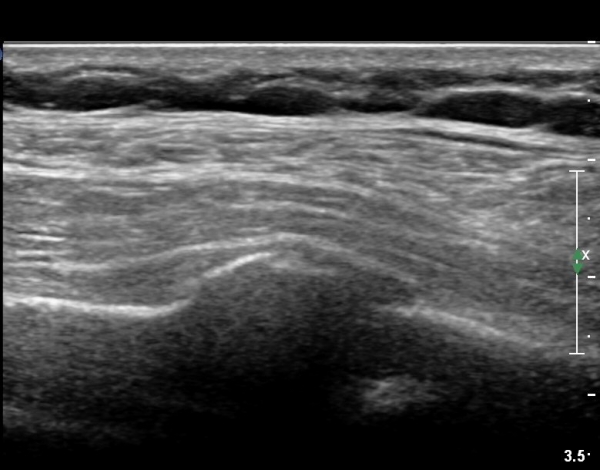

on moving of prove a little, there is bony protrusion(osteoblastic lesion) and hypoechoic(osteolytic)  lesion(image 2, 3, 4).

As like this case, visualization of osteoblastic lesion and osteolytic lesion in simultaneously  suggests a malignant mass.